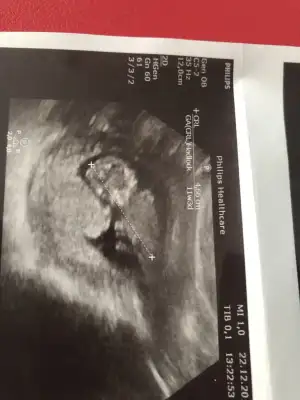

Slm güzel anneler bizde 11+1haftalik olduk bizede bir tahmin edermisiniz

Ikra meyra bu ultrasonlara gore bebek hangi tarafda ve cinsiyet tahmini ney.

Bunlarda ayni.